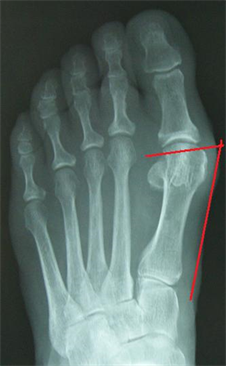

Figure 12. (a) Patient Nr. 3. Hallux valgus, pathologic DMAA; (b) Patient Nr. 3 Elevation of the Ist metatarsal of 3 mm.

Figure 15. Patient Nr. 3. The elevation of the I metatarsal was equalized by plantarization of the head of 3 mm.